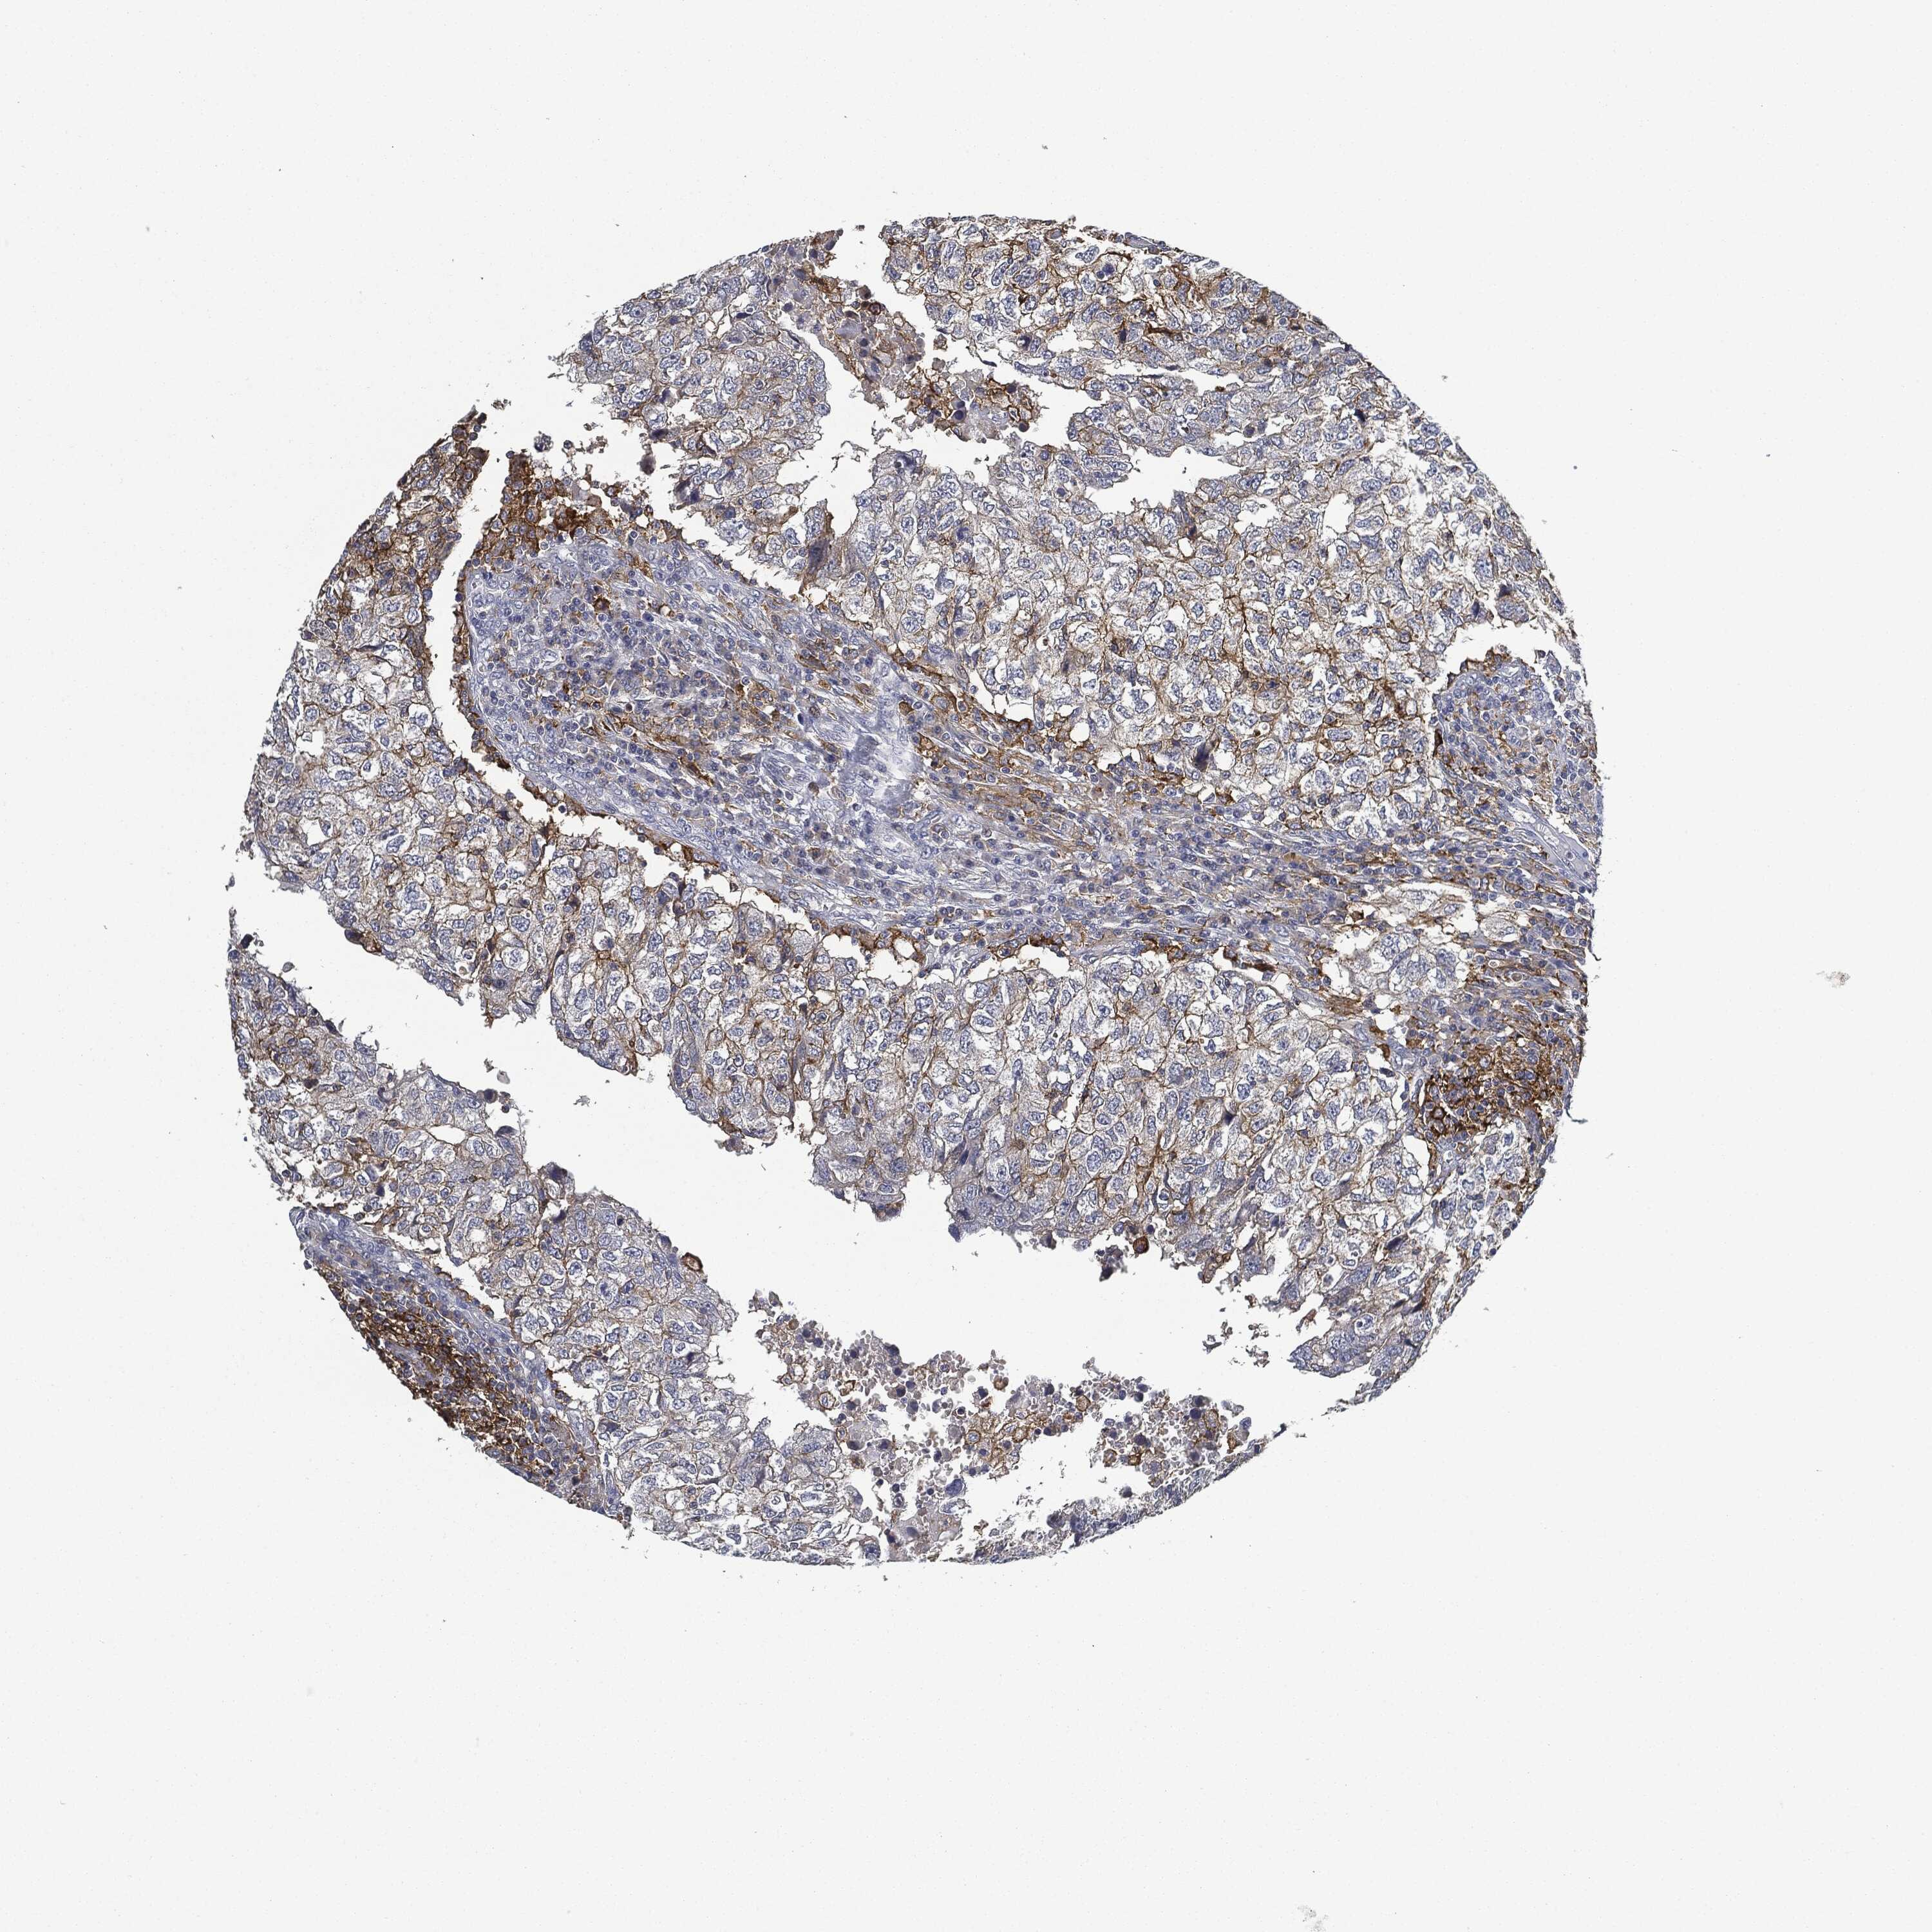

BRCA TCGA BRCA VALIDATION PROTEIN EXPRESSION

ANTIBODIES

AND

VALIDATION